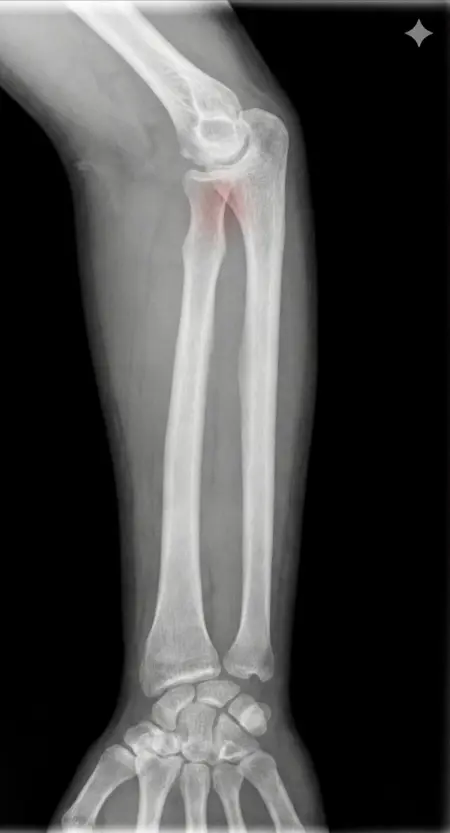

アートや写真の編集用に設計されたFlux Kontextのようなモデルを、医療画像、たとえば「単純な」骨折の赤色マーキングに使用できるか?

即答:面白い結果を出すが、過剰に反応し、医療ツールとしては信頼性に欠ける。これはアイデアを試すためのプロトタイプに過ぎない。

テスト結果:

- 偽陽性 ≈ 24%

- 骨折検出 ≈ 20%

感度モード(検出を優先、ノイズ多め)

- Euler、15ステップ、Karras

- Denoise:1.0

結果:

- 偽陽性 ≈ 80%

- 骨折検出 ≈ 86%

さらに攻撃的な設定(例:rk beta57、Denoise 1.0)では、**偽陽性100%、検出100%**という馬鹿げた結果に:すべてを赤で塗りつぶし、健常部もほぼすべて骨折と誤認する。未経験の目には区別がつかない。

Civitai用に作成した、100% AI生成の合成ミニデータセット(健康なX線10枚、骨折のあるX線10枚)でテスト:

- 健康な骨での偽陽性:100%

- 骨折検出:≈ 45%